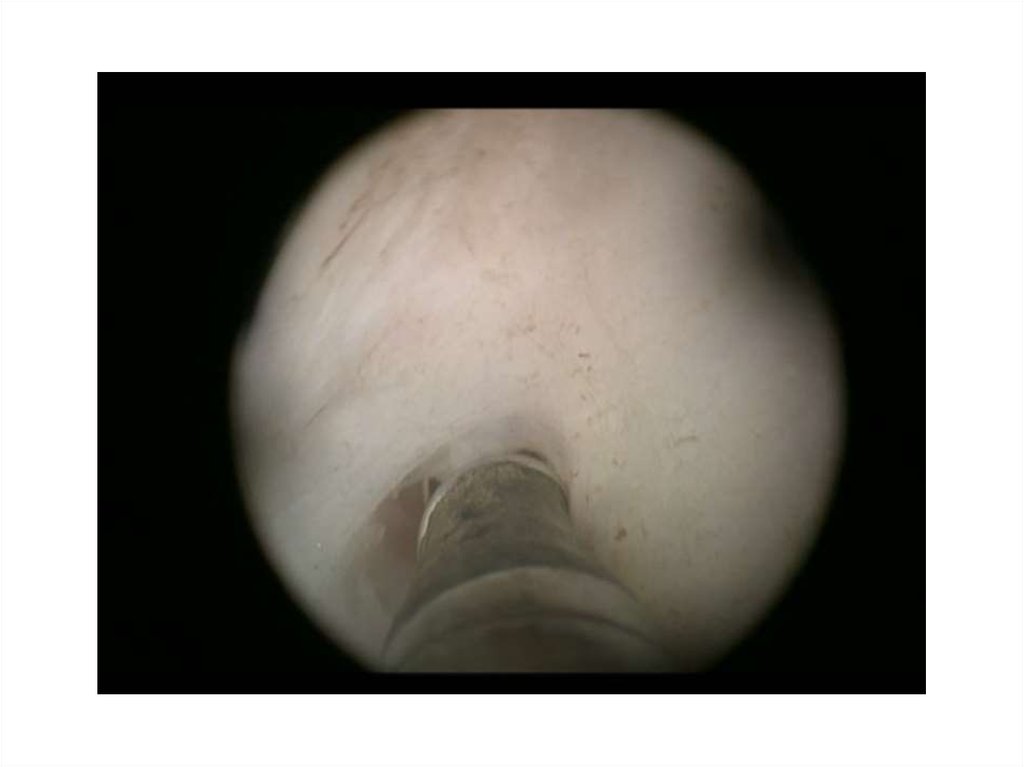

8. Кузнецов В.А. 59лет

• 13.11.14 – лазерная энуклеация ГПЖ

• 26.10.15 – ТУР шейки мочевого пузыря

• С января 2016 года отмечает ухудшение

качества мочеиспускания